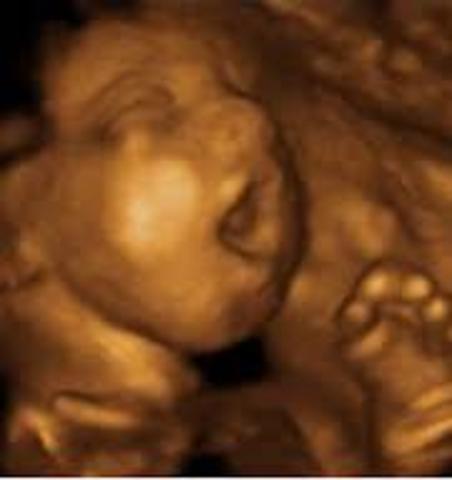

• Semana trigecimo segunda de gestación

Semana trigecimo segunda de gestación

En la semana 32 de embarazo tu bebé y todo su organismo ya están preparándose para lo que será la vida fuera de la placenta que los ha albergado todos estos meses. Medirá unos 47 centímetros y puede que llegue a pesar unos dos kilos.

Los riñones de tu bebé producen orina y sus pulmones comienzan a respirar, su cerebro continúa creciendo y las uñas ya llegan a la punta de sus dedos, por lo que deberás cortárselas al poco tiempo de nacer. Su rostro también es más expresivo y a veces sacará la leng